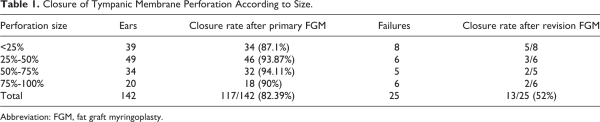

The inclusion criteria included perforation size >25% of the surface of the pars tensa of the TM, absence of infection or otorrhea at surgery, and lack of spontaneous closure at the 6-month follow-up. The exclusion criteria were the presence of cholesteatoma, attical pathology, perforation without clear margins, wet appearance of the mucosa in the tympanic cavity, presence of an acute infection, ear discharge in the 3 months before surgery, or signs of ossicular inconsistency (Figure 1).

Figure 1

Perforated tympanic membrane.